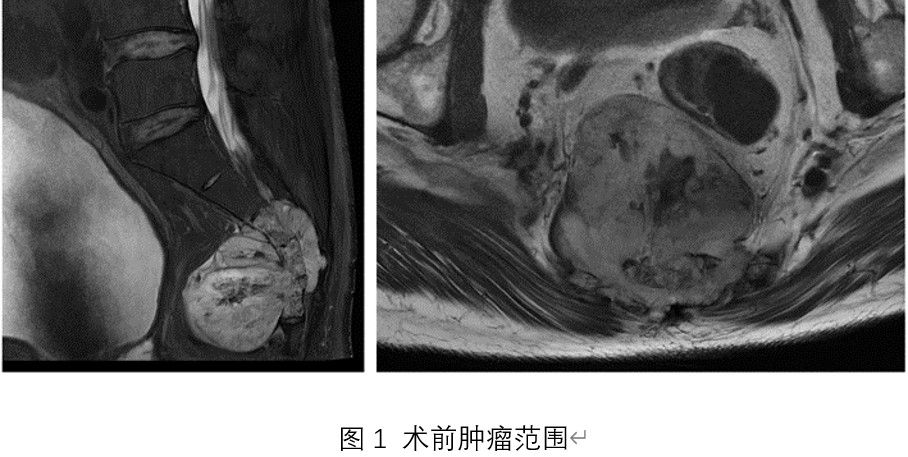

入院后,脊柱与骨肿瘤病区王栋主任牵头,赵波副主任医师、郭帅主治医师团队仔细检查,全面评估。超声穿刺活检提示脊索瘤(经典型),影像检查提示肿瘤位于第3、4骶椎,大小约6.2cm×6.7cm×6.4cm,突入盆腔压迫直肠,近端第2骶椎部分骨质已破坏,侵犯双侧骶2及以远神经根。

针对这一复杂病例,治疗团队迅速启动多学科协作(MDT)机制,发挥多科室集群协作优势,针对杨先生的病情,联合神经外科、麻醉科、影像科、烧伤整形外科、泌尿外科、普通外科等多学科力量,术前充分讨论,按照预定的顺序分阶段实施一系列治疗措施,即所谓“序列治疗(Sequenced Therapy)”,通过系统化、规范化的治疗流程,最大限度地恢复患者的功能,改善生活质量。经反复推敲,最终确定了“后路Mercedes-Benz切口骶骨脊索瘤en bloc切除术+切口创面负压封闭引流技术(VSD)+二期膀胱造瘘/肠造口术”的个体化方案。